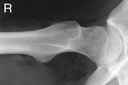

Alternative projection if both limbs have limited movement and the inferosuperior projection cannot be obtained

• Patient supine, affected side near edge of table with both legs fully extended

• Provide pillow for head, and place arms across superior chest.

• Maintain leg in neutral (anatomic) position.

• Rest IR on extended Bucky tray, which places the bottom edge of the IR about 2″ (5 cm) below the level of the tabletop.

• Tilt IR approximately 15° from vertical and adjust alignment of IR to ensure that face of IR is perpendicular to CR to prevent grid cutoff.